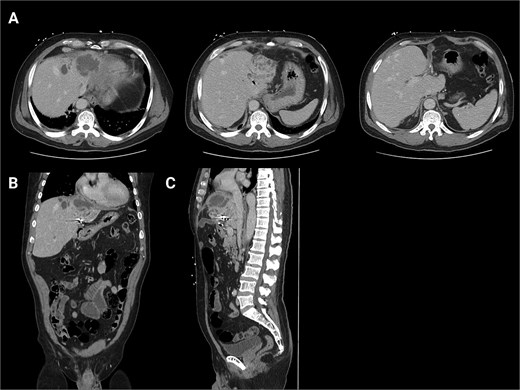

He was seen in the clinic 6 days later. At that time, he reported worsening abdominal pain and orthopnea. Repeat imaging showed that the hepatic abscess was stable in size, but the pericardial effusion had worsened and that the hepatic abscess had broken through the right hemidiaphragm (Fig. 4). Given his multiple instances of failed management, HPB Surgery elected to perform diagnostic laparoscopy. A TTE was performed, which showed a loculated pericardial effusion. Cardiothoracic Surgery (CTS) was consulted to see if drainage was indicated. They deemed that a pericardial window was needed, but it would depend on the outcome of the hepatic abscess drainage.

Second readmission imaging—CT of the chest in the axial, sagittal, and coronal views. These demonstrate that the abscess has eroded through the diaphragm and now abuts the pericardium. Additionally, it shows a worsening of the pericardial effusion, concerning for abscess communication.